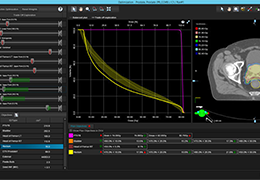

分析智能。

这些功能利用数字控制面板分析运营、业务和临床绩效。

使管理员能够跟踪关键参数,包括平均曝光率、拒绝的影像和探测器统计信息。

帮助确定需要改进的方面,支持为员工和部门制定适当的改进计划。